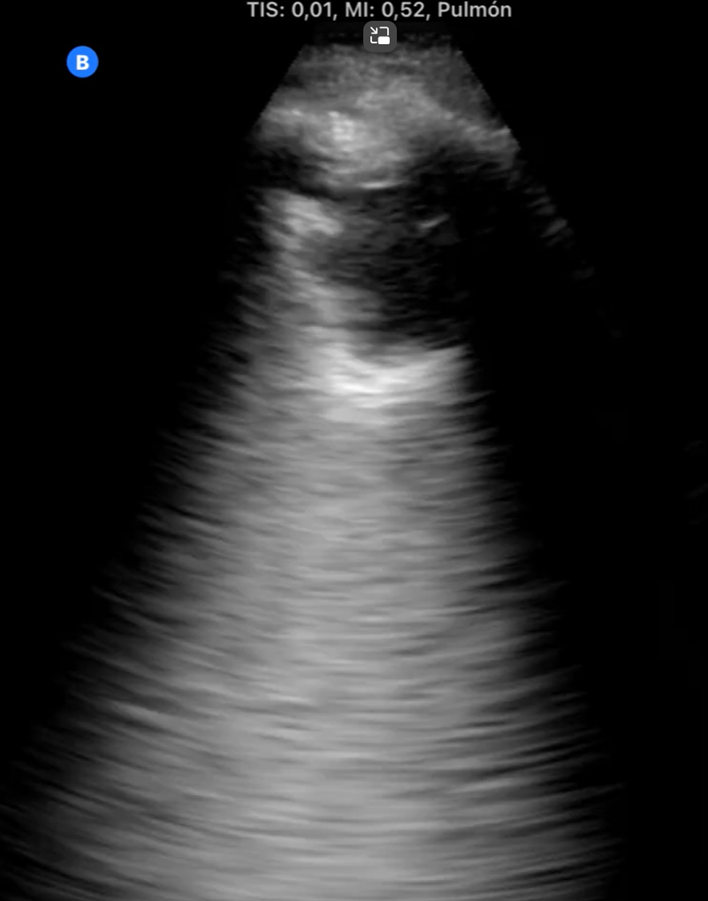

Hombre de 82 años que durante consulta de revisión tras caída evidenciamos disnea y taquipnea: TEP agudo bilateral central.